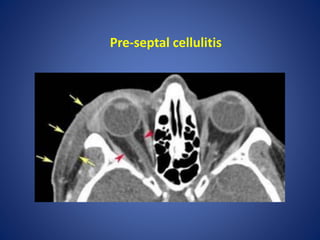

Orbital and periorbital cellulitis

It is important to differentiate between orbital and periorbial

cellulitis, as this has theraputic and prognostic implications:

1. peri-orbital cellulitis (pre-septal cellulitis) is limited to the soft

tissues anterior to the orbital septum. This condition is often

managed with oral antibiotics

2. orbital cellulitis refers to a post-septal infection (i.e. is behind or

extends posterior to the orbital septum). This is a more serious

condition requiring hospitalisation and parental antibiotics.

Complications such as intraorbital abscess formation may require

surgical intervention

Pre-septal cellulitis

• #38 Inflammation and swelling of soft tissues anterior to, but not posterior to the orbital septum, consistent with periorbital cellulitis.

• #39 Axial contrast-enhanced CT image of the orbit shows soft tissue thickening of the right preseptal region (between arrows). The retroorbital fat is normal (arrowheads).

• #40 CT (C+ arterial phase) Increased attenuation of fat planes of left peri-orbital area with extraconal extension along the medial rectus muscle.